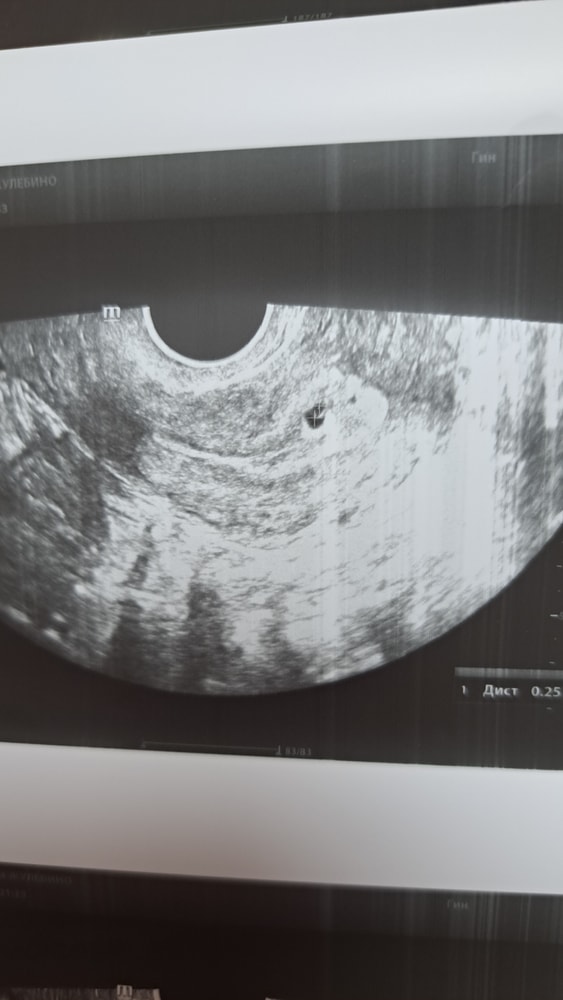

Из за розовой прожилки пришлось бежать раньше,потому что я честно испугалась. В итоге все хорошо. Увидели жм и эмбриончик. Срок 5+6, узи на 3-4 недели написала. Но так как врач не гинеколог,а кардиолог, то я пойду еще 16 к гинекологу и там ещё посмотрю бусинку🥰